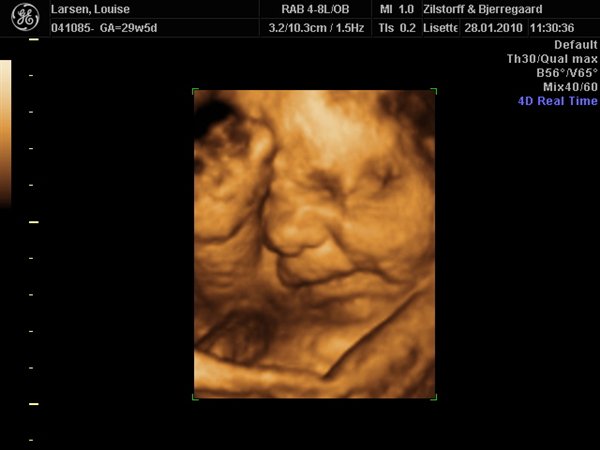

Vi har været til 3D/4D Scanning idag. Og sikke en vild oplevelse.... Har aldrig (udover min fødsel af Nicklas) prøvet noget så stort!

Her er lidt billeder: